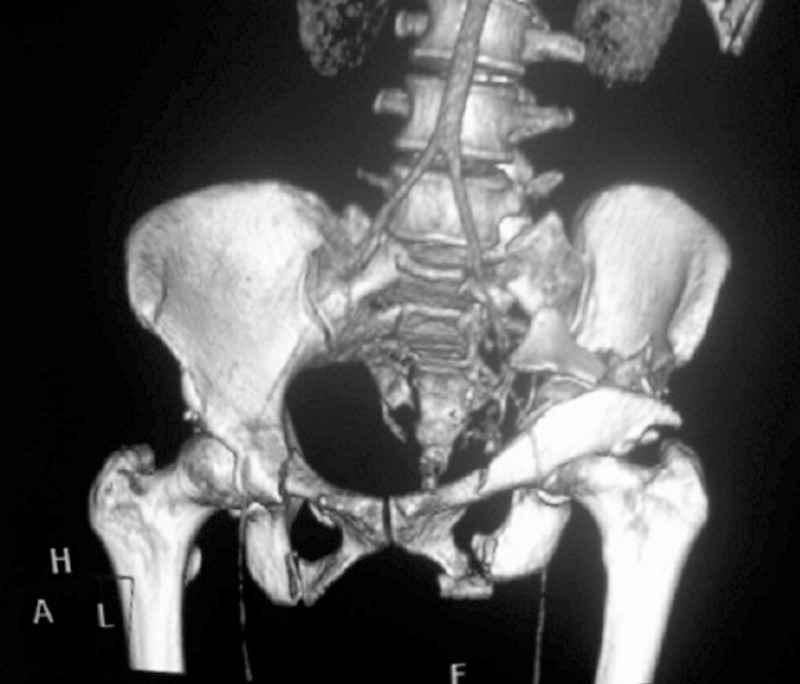

This patient has extensive and complicated skeletal injuries...much more data (such as additional relevant images and clinical information regarding the soft tissues and overall patient status) would help us formulate an informed plan.

The sacral pattern alone is quite difficult and seems to be some version of an H-pattern, but I can’t tell from these films.

The soft tissues are also in mild condition, buttock hematoma and probably a Morel-Lavalle. I send some more CT images. There are some conminution in the posterior column (I don’t have images now). The patient is scheduled for surgery next Monday. The plan is percutaneous sacral fixation and then ilioinguinal approach .

I am a huge fan of closed reduction and percutaneous posterior pelvic fixation, but that particular sacral injury warrants an open reduction.

I’d begin with that in order to have a high quality osseus foundation for subsequent acetabular repair.